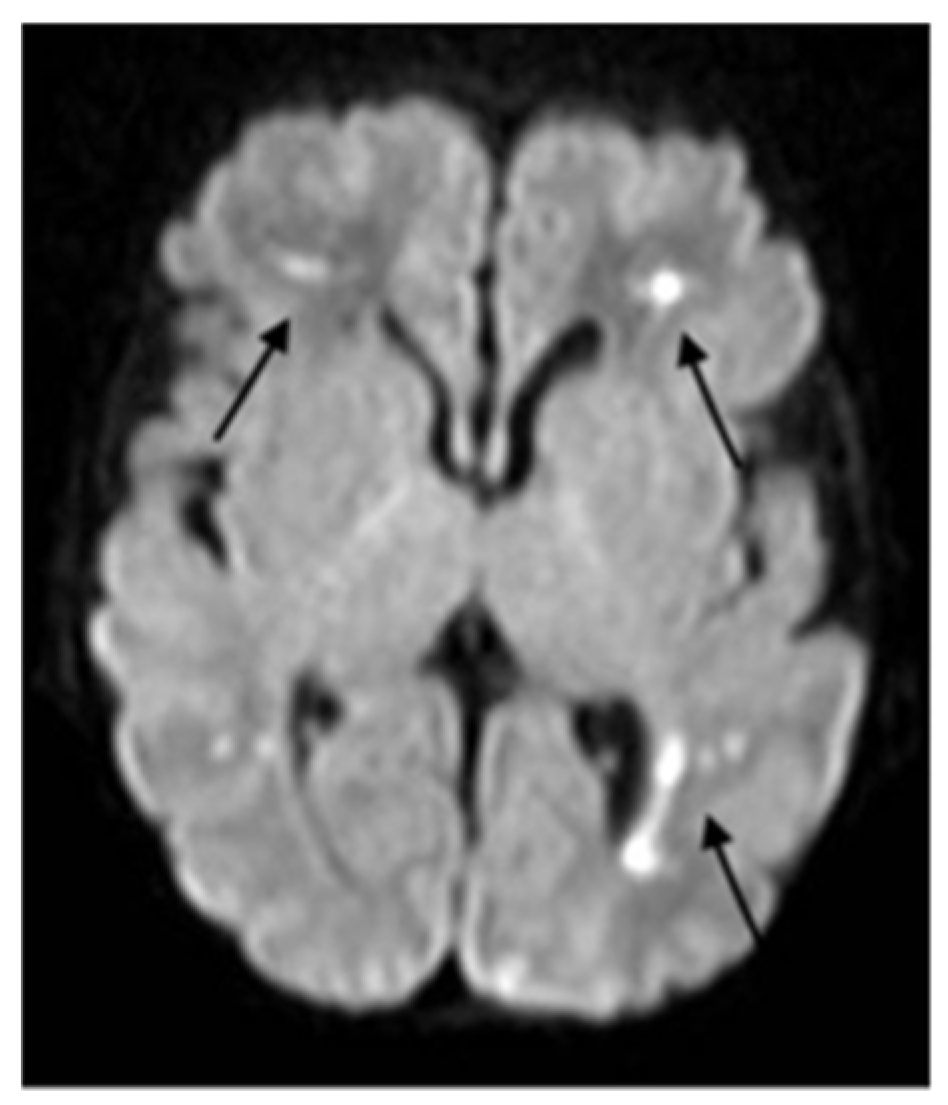

2. Case Description